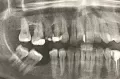

Проблема такова: в один момент стало казаться, будто между двумя задними зубами что-то есть. Кажется, что один из них шатается. Тот же самый зуб при прикусе начинает болеть, причем очень сильно. Даже при прикосновении к зубу возникает жуткая боль. Жевать этой стороной очень больно.

Боль при накусывании скорее всего говорит о хроническом процессе (периодонтит).

Чтобы выявить проблему необходимо обратиться к врачу на очный прием, проделать рентген-анализ и поставить диагноз. Рекомендую не тянуть, так как есть вероятность потери зуба.